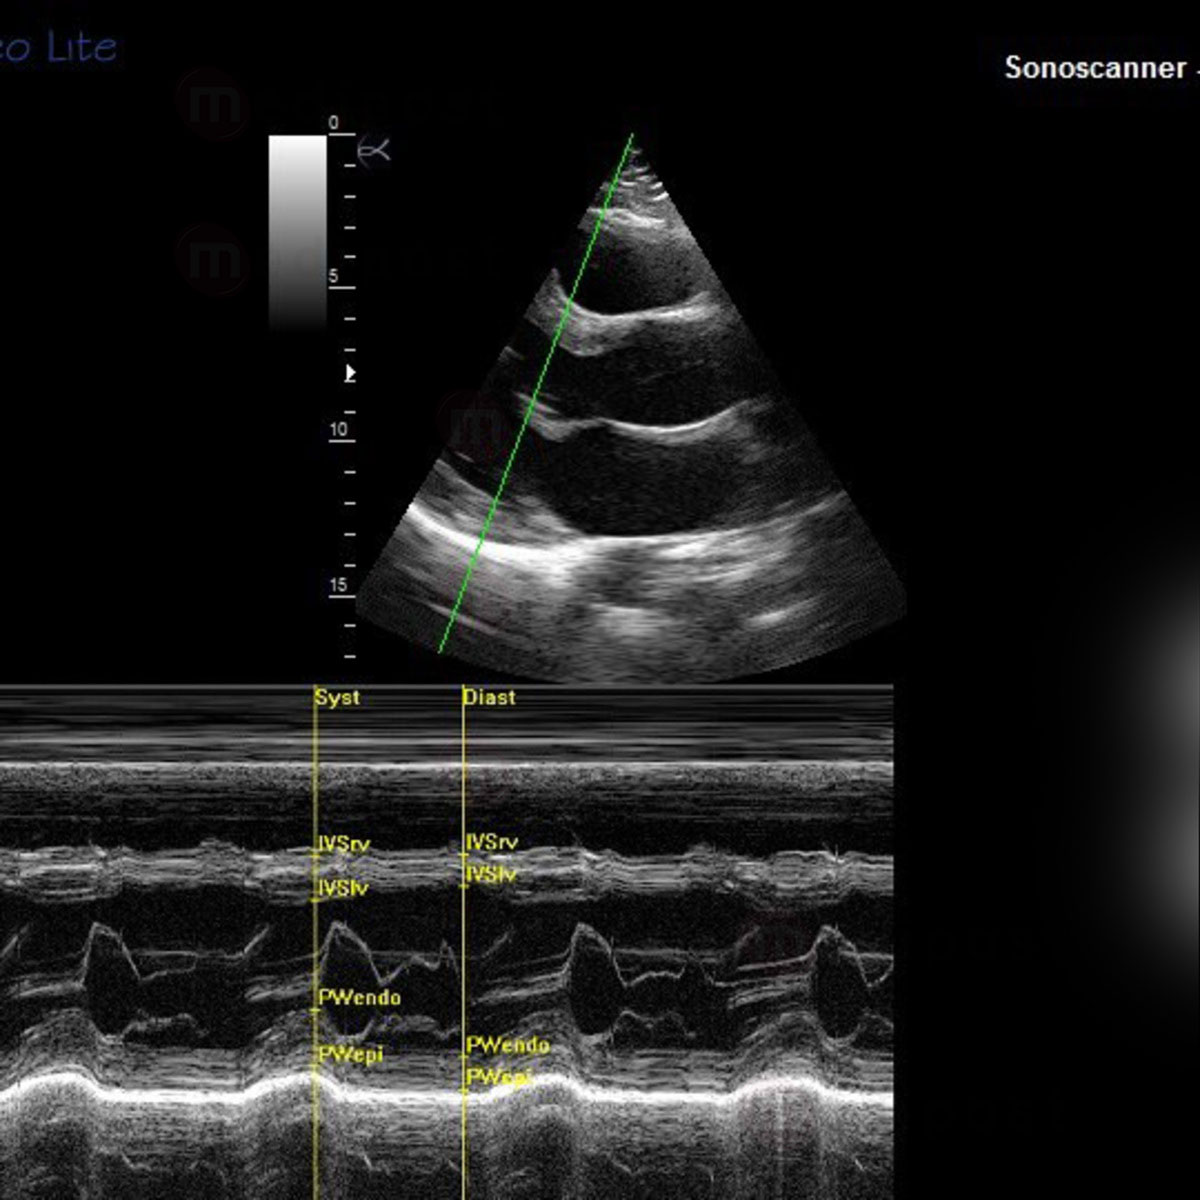

Modes d'imageries :

- Mode B (2D)

- Mode TM

- Imagerie Harmonique tissulaire

Caractéristiques haut de gamme :

Avec Orcheo Lite, bénéficier des toutes dernières technologies numériques

- Sonde sectorielle Phased Array 1,5-5 Mhz (Pédiatrie, Urologie, MSK, Anesthésie, Pédiatrie, Cardiologie, Urgences, Transcranien, Pédiatrie)